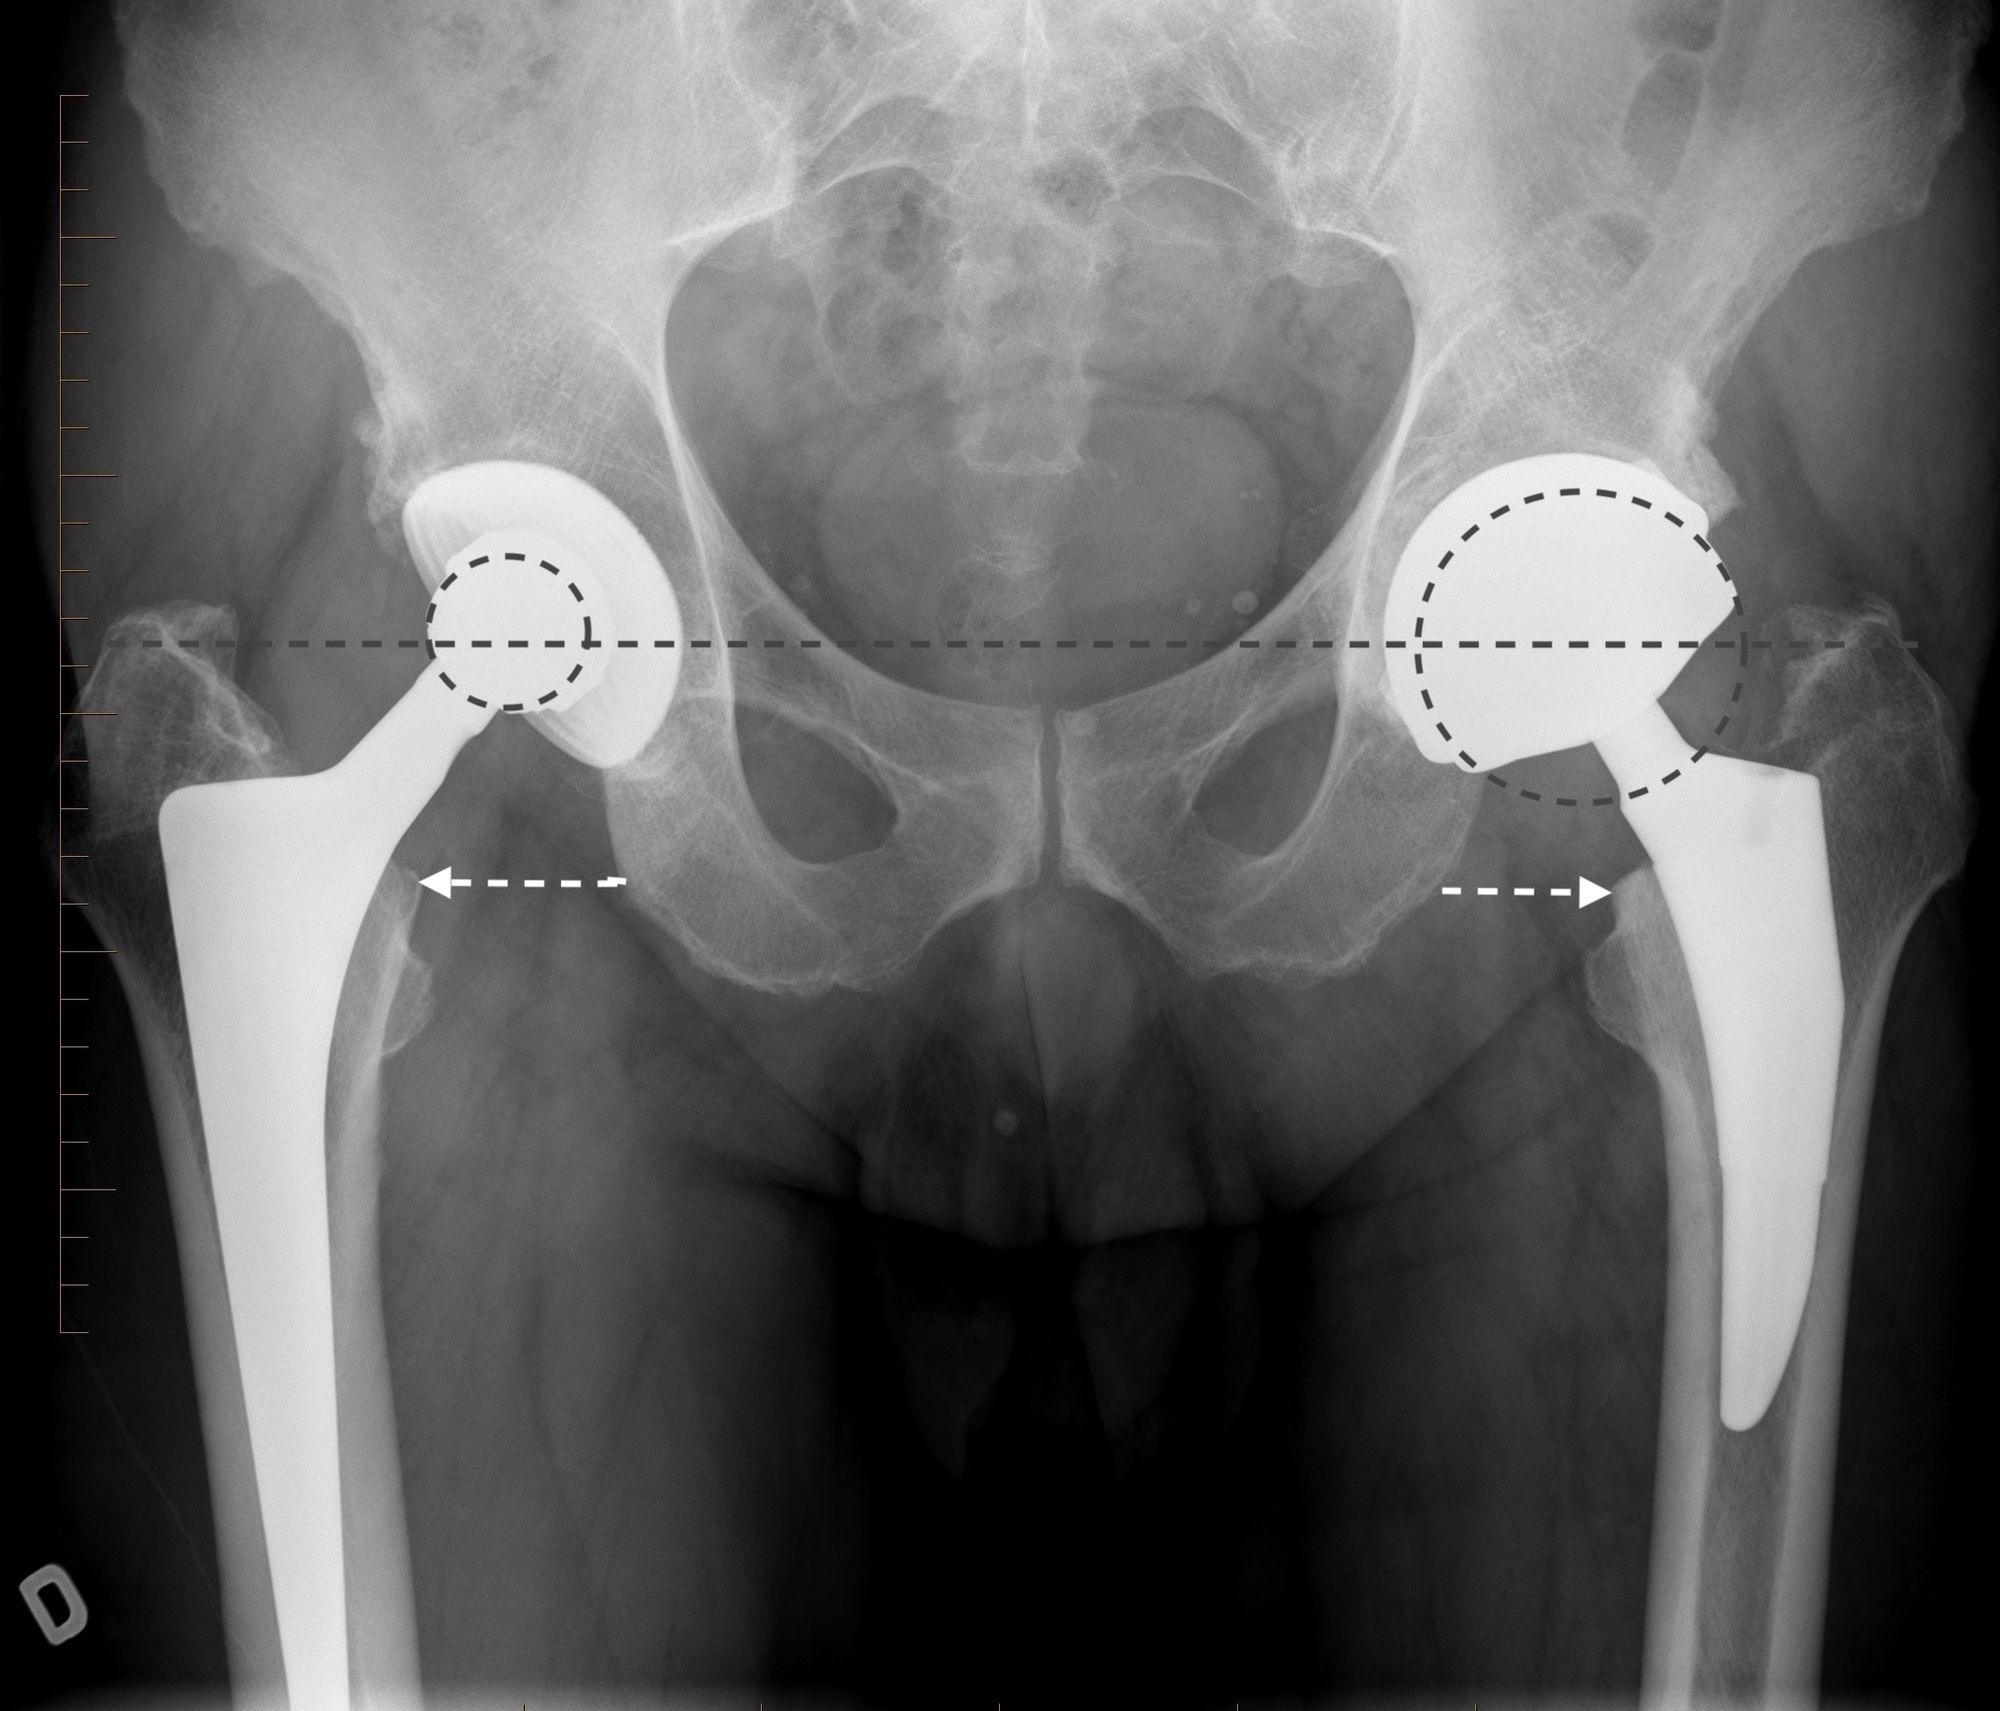

Using an LDH THA allows unrestricted movement after THA, for all types of surgical approaches. Vendittoli’s group in Canada does not impose any postoperative ROM restrictions for the posterior surgical approach, as it simplifies the patient education process, boosts their confidence during rehabilitation, and facilitates bilateral procedures[15,16]. LDH monobloc DM is especially interesting for many older women with large thighs and a small acetabular cavity (<50mm, Fig. 7).

In these cases, standard bearing diameters are prone to instability. With an LDH, a DM design provides optimal implant stability for these not-so uncommon patients. Moreover, with LDH we do not impose any activity restrictions in the long term. LDH CoC THA offers a major benefit for many active individuals since they can return to their regular jobs (e.g. plumber, roof worker, police officer, fireman) as well as for those who want to practice sports like rock climbing, kayaking, water skiing and martial arts.

Given the single neck diameter of most femoral stem designs, the head–neck ratio increases proportionally with the head diameter. Theoretically and clinically, this leads to a greater hip range of motion [18,19]. In addition, due to a supraphysiological arc of motion, extraarticular impingement is the first to occur whilst inter-component impingement is rare. Consequently, less-than-optimal implant positioning can be much better tolerated[20]. This is an important point considering the extent of surgical indications for patients with primary or secondary anatomical deformations (e.g. dysplasia, acetabular retroversion, previous pelvic osteotomy, post traumatic), because achieving an optimal implant position is often challenging (Fig. 7).

For the older, more sedentary and those with a shorter life expectancy, DM LDH THA is the ideal alternative (Figs 7 and 8).